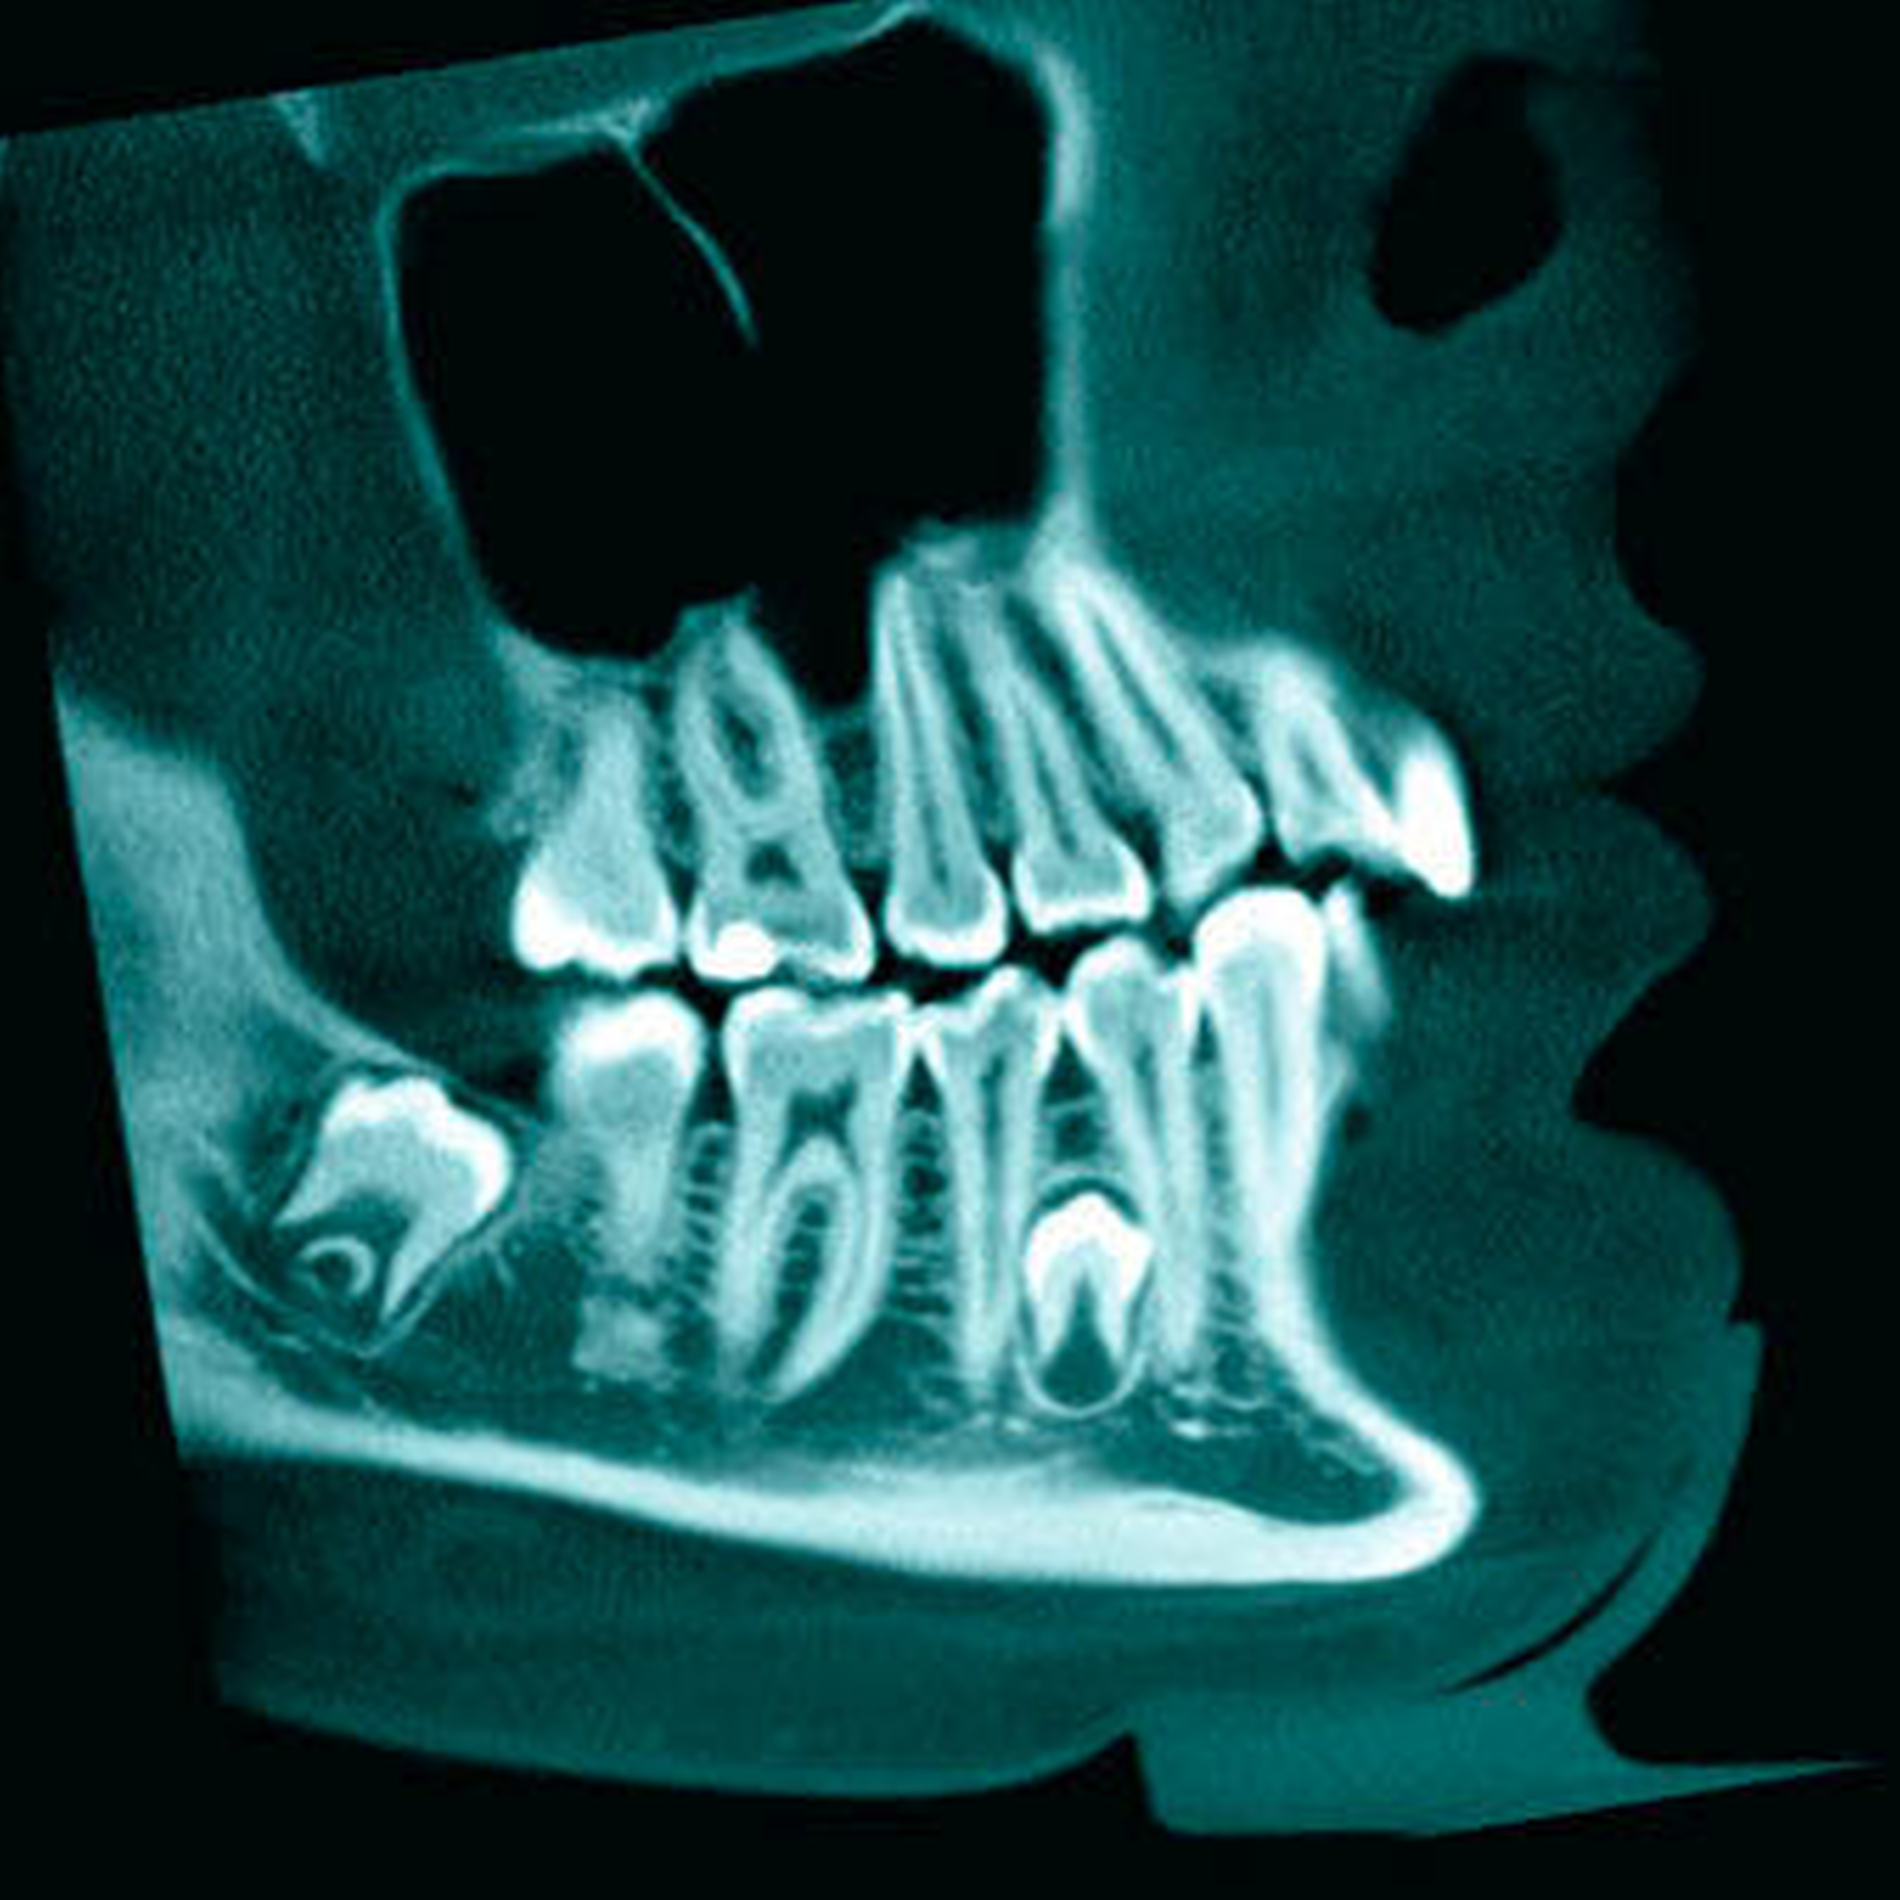

Die exakte Lokalisierung von überzähligen Zähnen ist für die Diagnose, den Behandlungsplan und vor einem zahnärztlich- chirurgischen Eingriff von großer Bedeutung. Traditionell wurden überzählige Zähne radiologisch mittels 2D Bildgebung wie Einzelzahnröntgenbildern (inklusive Aufbissaufnahmen), Panoramaschichtaufnahmen (PSA) und auch Fernröntgenbildern (FR) evaluiert und lokalisiert [Von Arx, 1990; Garvey et al., 1999; Rajab Hamdan, 2002]. Trotz all den oben genannten radiologischen Verfahren kann die Bestimmung der genauen 3D Position des Zahnes im Kiefer und insbesondere die Evaluation von Wurzelresorptionen an benachbarten Zähnen problematisch sein. Daher wurde vor bald drei Jahrzehnten die Computertomografie (CT) als weiterführende diagnostische Methode vorgeschlagen [Ericson Kurol, 1988; Traxler et al., 1989; Krennmair et al., 1995], welche sich aber bedingt durch die relativ hohen Kosten und die nicht unbedeutende Strahlendosis nicht als Methode der Wahl durchsetzten konnte [Chaushu et al., 2004; Liu et al., 2007]. Nach Einführung der digitalen Volumen- tomografie (DVT) in der Zahnmedizin [Mozzo et al., 1998] wurde die Indikation und Eignung dieser Methode zur exakten Lagebestimmung bei überzähligen Zähnen mehrfach untersucht und als radiologische weiterführende Methode der Wahl bei unklaren Fällen empfohlen [Liu et al., 2007; Kapila et al., 2011; Dula et al., 2014; Mossaz et al., 2014]. Ein nicht unbedeutender Vorteil ist, dass bei der DVT – besonders bei kleinen und mittleren Feldgrößen – bedeutend weniger Strahlung emittiert, als bei einer traditionellen CT-Untersuchung erzeugt wird [Harris et al., 2012; Pauwels et al., 2012; Bornstein et al., 2014]. Durch die 3D-Visualisierung der Kieferbereiche mittels DVT erhält man Informationen in allen drei Ebenen und erhöht damit die diagnostische Genauigkeit bei der Untersuchung von retinierten Zähnen bei kieferorthopädischen Patienten [Becker et al., 2010; Pazera et al., 2011; Lai et al., 2014], was vor einem chirurgischen Eingriff von Bedeutung ist [Becker et al., 2010].

Dies gilt besonders, wenn sich überzählige Zähne in der Nähe von vitalen anatomischen Strukturen wie dem Nasenboden, dem nasopalatinalen Kanal, dem Foramen infraorbitale, der Kieferhöhle, dem Mundhöhlenboden, dem Foramen mentale oder dem Mandibularkanal befinden [Dula et al., 2014; Mossaz et al., 2014]. In zwei Studien, welche zur Abklärung der Lage von überzähligen Zähne jeweils eine radiologische Abklärung mittels DVT durchführten [Liu et al., 2007; Mossaz et al., 2014], wurde berichtet, dass eine beachtliche Anzahl von Mesiodentes einen engen Kontakt zum Nasenboden und / oder zum nasopalatinalen Kanal zeigten.

In einer chinesischen Untersuchung von Liu und Mitarbeiter (2007) wurde die Qualität der Darstellung von Wurzeln und Kronen bei überzähligen Zähnen mittels DVT, PSA und FR verglichen. Eine hervorragende Bildqualität wurde bei der DVT für die Kronen und Wurzeln in 98 Prozent beziehungsweise 94 Prozent der Fälle, bei der PSA in 72 Prozent und 40 Prozent und bei FR in 52 Prozent und sechs Prozent der Fälle gefunden. Die 3D-Bildgebung mittels DVT ermöglicht es auch, detaillierte Informationen über Prävalenz und Ausmaß von Wurzelresorptionen an Nachbarzähnen zu gewinnen [Alqerban et al., 2009; Katheria et al., 2010; Botticelli et al., 2011; Alqerban et al., 2011a; Lai et al., 2013]. Gegenüber traditioneller alleiniger 2D-Bildgebung zeigte sich bei Kieferorthopäden, dass sich diese durch die Beurteilung von zusätzlich angefertigten DVT-Bildern in der Diagnosefindung und Behandlungsplanung sicherer fühlten [Haney et al., 2010]. Eine in-vitro-Studie an menschlichen Schädeln zeigte zudem keine signifikanten Unterschiede zwischen den verschiedenen DVT-Systemen im Hinblick auf die Beurteilung der Schwere der Wurzelresorptionen auf [Alqerban et al., 2011b].

Zusammenfassend soll nach einem radiologischen Zufallsbefund oder der Bestätigung eines Verdachts auf einen überzähligen Zahn das entsprechende Einzelröntgenbild/ PSA (Polymerase Kettenreaktion) jeweils zuerst eingehend beurteilt werden. Sollten trotz klinischer Untersuchung und radiologischer 2D-Untersuchung Fragen nach der genauen Lage (bukkal/oral) oder auch der Beziehung zu benachbarten relevanten anatomischen Strukturen offen bleiben, kann nach Rücksprache mit dem Patienten eine weiterführende 3D-Untersuchung sinnvoll sein. Für die Abklärung von überzähligen Zähnen sollte dabei die DVT gegenüber einem CT bevorzugt werden. Wenn ein DVT durchgeführt wird, sollten möglichst optimale Einstellparameter gewählt werden, dies auch im Sinne des ALARA-Prinzips [AsLowAsReasonablyAchievable; Bornstein et al. 2014]: Auswahl der kleinst-möglichen Fenstergrößen (in der Regel kleine oder mittlere Fenstergrößen) sowie Auswahl der geeigneten Einstellungen (kV, mA, hochauflösend versus „low dose“ Protokolle, das heißt, Reduktion der Anzahl der Aufnahmen pro Umlauf sowie der Belichtungszeit, 180° versus 360°-Umlauf).